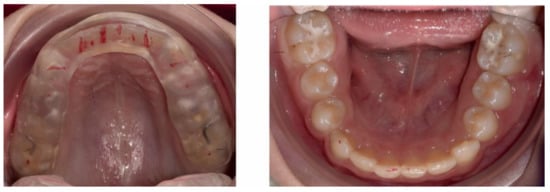

3. Results